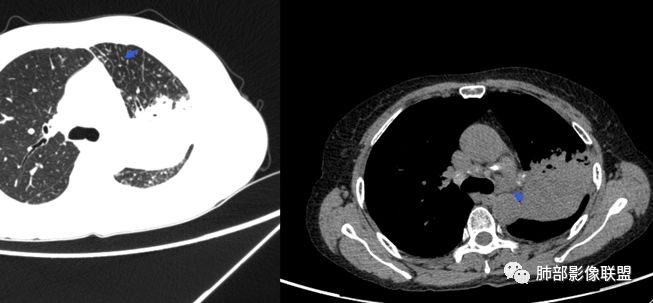

病灶远端有扩张支气管,树芽,实变,纵隔肺内淋巴结钙化,考虑肺结核。

下叶背段有树芽

左肺占位,边界平直,无明显膨胀性,炎性首先考虑,支气管壁不光滑,考虑气道来源,青年女性,有地热,乏力,体重减轻,结合病灶周围有树芽征,我考虑结核!

整个上叶尖后段阻塞性肺不张的表现,从强化来看没有异常结节状或肿块样强化,肿块内部点状钙化、纵隔多发小淋巴结、下叶背段有树芽征,整体来看支持肺结核,让人不放心的是最后一幅冠状位重建的图像尖后段支气管堵了,而且有轻度的隆起,所以很难除外粘液表皮样癌(女性,鳞癌可能性小),如果是我写报告肯定会建议纤支镜检查

晨读:左肺上叶实变,边缘不整,部分膨隆,其内支气管有狭窄有扩张,周围小叶间隔增厚,左肺下叶背段可见气腔结节,树芽征,边缘模糊,肺门及纵膈淋巴结钙化,考虑结核。鉴别肺炎型肺癌。

树芽征、小叶间隔增厚,淋巴结, 内部血管走形自然

分析:支气管粘液栓、支气管堵塞处萎缩、钙化,支气管通畅处部分扩张,树芽征——提示结核。

1.双肺多发病灶,结节影、树丫影,边缘分布……病灶符合继发性肺结核。